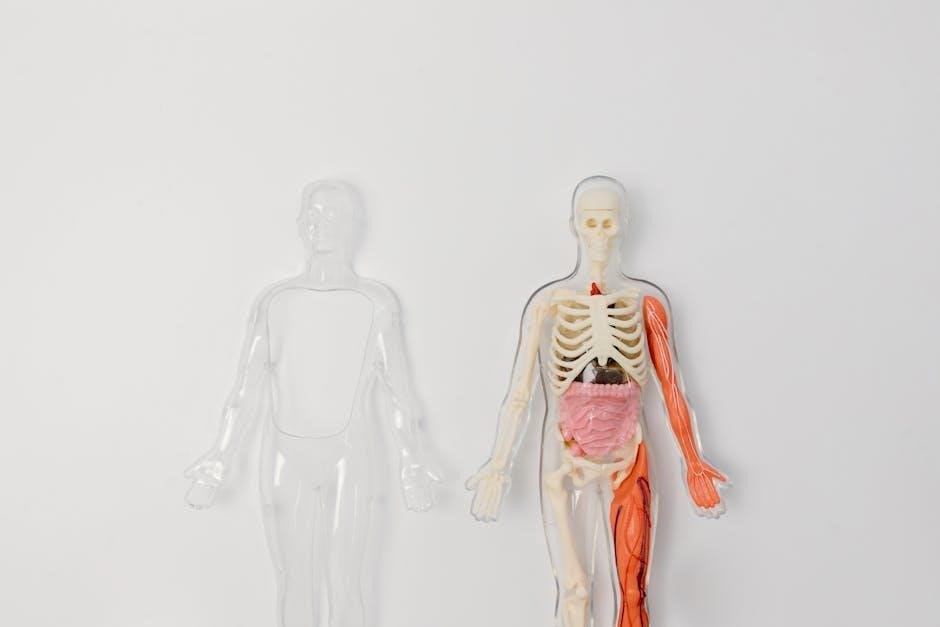

Human bodies exhibit remarkable complexity, comprised of eleven interconnected systems working in harmony to sustain life and perform essential functions.

Skeletal System

Bones provide structural support, protect vital organs, and enable movement via joints. This system also facilitates blood cell production within bone marrow.

Bone Structure and Support

Bones aren’t simply solid masses; they possess a complex internal architecture providing incredible strength with minimal weight. Compact bone forms the hard outer layer, while spongy bone, filled with spaces, offers flexibility.

The skeletal system’s primary role is providing a rigid framework supporting the body against gravity. Bones also protect delicate internal organs, like the brain within the skull and lungs within the ribcage. Furthermore, bones serve as attachment points for muscles, enabling locomotion and maintaining posture.

Muscular System

Muscle tissues—skeletal, smooth, and cardiac—facilitate movement, maintain posture, and generate heat, enabling essential bodily functions and overall physical activity;

Types of Muscle Tissue

The muscular system showcases three distinct tissue types: skeletal, smooth, and cardiac. Skeletal muscle, attached to bones, enables voluntary movements. Smooth muscle, found in organ walls, controls involuntary actions like digestion. Cardiac muscle, exclusive to the heart, powers continuous, rhythmic contractions.